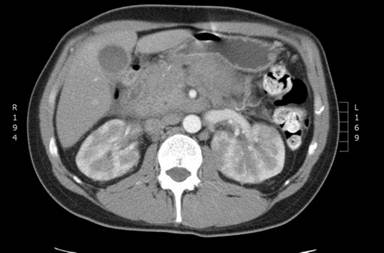

A 39-year-old man presented with a 4-month history of 6 kg weight loss and a 6-week history of upper abdominal pain radiating to the back with nausea and vomiting. He had no significant past medical history and apart from jaundice and tenderness in the upper abdomen, examination was normal. Laboratory investigations showed a haemoglobin concentration of 13.5 g/dL (reference range: 11.5-16.5 g/dL), total white cell count of 5.0x109/L (reference range: 4-11x109/L) with a normal differential white cell count, bilirubin of 6 µmol/L (reference range: 3-21 µmol/L) , alanine transaminase of 43 IU/L (reference range: 10-60 IU/L), and alkaline phosphatase of 175 IU/L (reference range: 25-125 IU/L). Computerised tomography (CT) showed a diffusely enlarged pancreas with dilatation of the common bile duct and intrahepatic biliary tree. The pancreatic mass measured 4 cm at the head of pancreas and 4.5 cm at the body. A single left para-aortic node of 1.7 cm was also found (Figure 1) but there were no other abnormalities. Radiologically, the differential diagnosis included autoimmune pancreatitis or primary pancreatic lymphoma, however, IgG4 levels, pancreatic autoantibodies and CA 19-9 measurements were unremarkable. Four weeks after the initial blood tests, bilirubin and alanine transaminase were stable but alkaline phosphatase had increased to 1,699 IU/L and the white cell count increased to 44x109/L. The blood film showed blast cells (33% of total white cell count) and subsequent bone marrow aspirate and trephine revealed a diagnosis of precursor B cell lymphoblastic leukaemia (Figure 2). Cytogenetics identified a t(4;11) chromosomal translocation with a mixed lineage leukaemia gene rearrangement.

Figure1. CT scan of the pancreatic mass at presentation. |